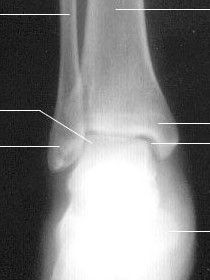

踝關節踝關節ankle joint

由脛、腓骨下端的關節面與距骨滑車構成,故又名距骨小腿關節。脛骨的下關節面及內、外踝關節面共同作成的“冂”形的關節窩,容納距骨滑車(關節頭),由於滑車關節面前寬後窄,當足背屈時,較寬的前部進入窩內,關節穩定;但在跖屈時,如走下坡路時滑車較窄的後部進入窩內,踝關節鬆動且能作側方運動,此時踝關節容易發生扭傷,其中以內翻損傷最多見,因為外踝比內踝長而低,可阻止距骨過度外翻。踝關節結核的治療

關節囊前後較薄,兩側較厚,並有韌帶加強。脛側副韌帶為一強韌的三角形韌帶,又名三角韌帶,位於關節的內側。起自內踝,呈扇形向下止於距、跟、舟三骨。由於附著部不同,由後向前可分為四部:距脛後韌帶、跟脛韌帶、脛舟韌帶和位於其內側的距脛前韌帶。三角韌帶主要限制足的背屈,前部纖維則限制足的跖屈。腓側副韌帶位於關節的外側,由從前往後排列有距腓前、跟腓、距腓後三條獨立的韌帶組成,連結於外踝與距、跟骨之間。距腓後韌帶可防止小腿骨向前脫位。當足過度跖屈內翻時,易損傷距腓前韌帶及跟腓韌帶。

踝關節屬滑車關節,可沿通過橫貫距骨體的冠狀軸做背屈及跖屈運動。足尖向上,足與小腿間的角度小於90°叫背屈,反之,足尖向下,足與小腿間的角度大於直角叫做跖屈。在跖屈時,足可做一定範圍的側方運動。